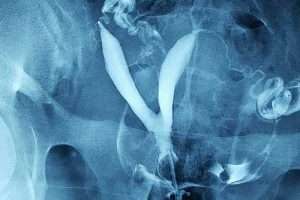

Normal HSG